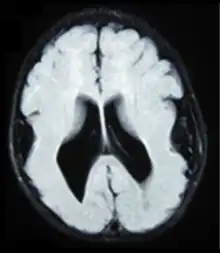

| Brain MRI, T1 weighted on a transversal plane, of an 8-month old boy with lissencephaly. Note the scarce and wide gyri, mostly on the parietal, temporal and occipital lobes, the absence of a true Sylvian fissure, and the augmented thickness of the gray matter. The boy had a severe developmental delay and seizures. | |